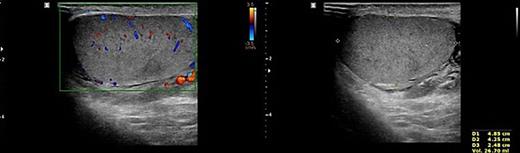

To prevent the patient from further self-injury, simple therapeutic restraint of both arms was performed with the patient’s consent, and sedative medication was administered. He was closely observed in the intensive care unit to monitor his hemoglobin and systemic conditions. Additional transfusion treatment was provided as needed. Psychiatric medicines including antipsychotics and sedatives (Clozapine 125–250 mg/day, haloperidol 2.5–5 mg, and lorazepam 1–2 mg/day) were prescribed by a psychiatrist. After 5 days of taking the psychiatric medication, the patient no longer reported the impulse to harm himself, and was able to release the simple restraint on both arms. No further self-harm occurred until he was discharged, presumably due to the proper effects of taking psychiatric medication. Anticoagulant agents (5 mg apixaban, twice per day), subcutaneous heparin injection (5,000 IU, twice per day), and alprostadil (10 mg, once per day) were given for circulation to prevent the thrombosis of vessels. On POD2 from the first operation, a testicular scan with technetium pertechnetate revealed the viability of the remnant left testis compared with the amputated right testis (Fig. 7). On POD4, contrast-enhanced CT showed the enhancement of the vessel into the testis (Fig. 8). On POD7, scrotum Doppler ultrasonography revealed the Doppler signal in the parenchyma of the testis (Fig. 9). Testosterone levels increased after the surgeries and normalized on POD5 (Fig. 10). He was discharged on POD9 without any skin complication (Fig. 6c). After discharge, he returned to our clinic for follow-up on POD13 and 23. On the visit, laboratory follow-up including testosterone and free testosterone was checked and confirmed as normal (Fig. 10).

Doppler ultrasonography of the patient. No other abnormality except mild fluid collection was shown on the left testis and epididymis.

We performed five examinations to check the viability of the replanted testis. First, in the operating room, we used indocyanine green after replantation (Fig. 4). Indocyanine green fluorescence perfusion showed testicular perfusion, which enabled the immediate checking of the viability of vessels. This procedure is appropriate for checking the viability of microscopic vessels that may be damaged during a milking test. Second, a testicular scan showed the viability of the testis (Fig. 7). One testis is markedly different from the lesion of orchiectomy. However, the scan resolution was low because of a wide range of arterial courses and the disturbance of the urethral catheter or bladder. Third, contrast-enhanced CT displayed the vascularity of the testis and the surrounding parts (Fig. 8). However, the shooting time to the enhanced phase could affect the failure of the vascularity of the testis. No protocol for this case has been established in our institute; therefore, CT was a nonspecific tool for testicular examination. Fourth, ultrasonography efficiently showed the vascularity inside the testis (Fig. 9). However, skin wound could inhibit or limit ultrasonography. Fifth, we indirectly checked the testicular function based on testosterone levels (Fig. 10). A laboratory examination should be performed continuously. However, this procedure could be limited among hypogonadal men, and the separate testicular function of each testis could not be easily identified. Nevertheless, these techniques will help determine the viability of the testis in specific situations.